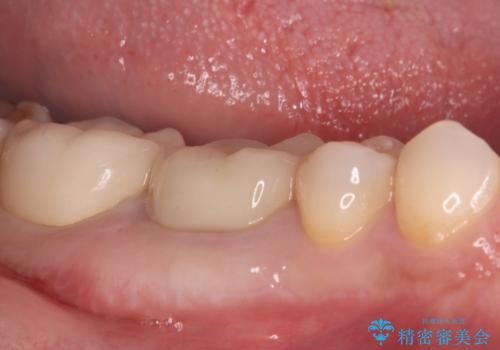

古い銀歯と中の虫歯をしっかりと取り除き、耐久性の高いセラミッククラウンで補強しました。

セラミックは見た目が美しいだけでなく、汚れがつきにくく、良好な口腔衛生状態を維持しやすくなり長期的に安心して使用できる状態へと整えることができました。